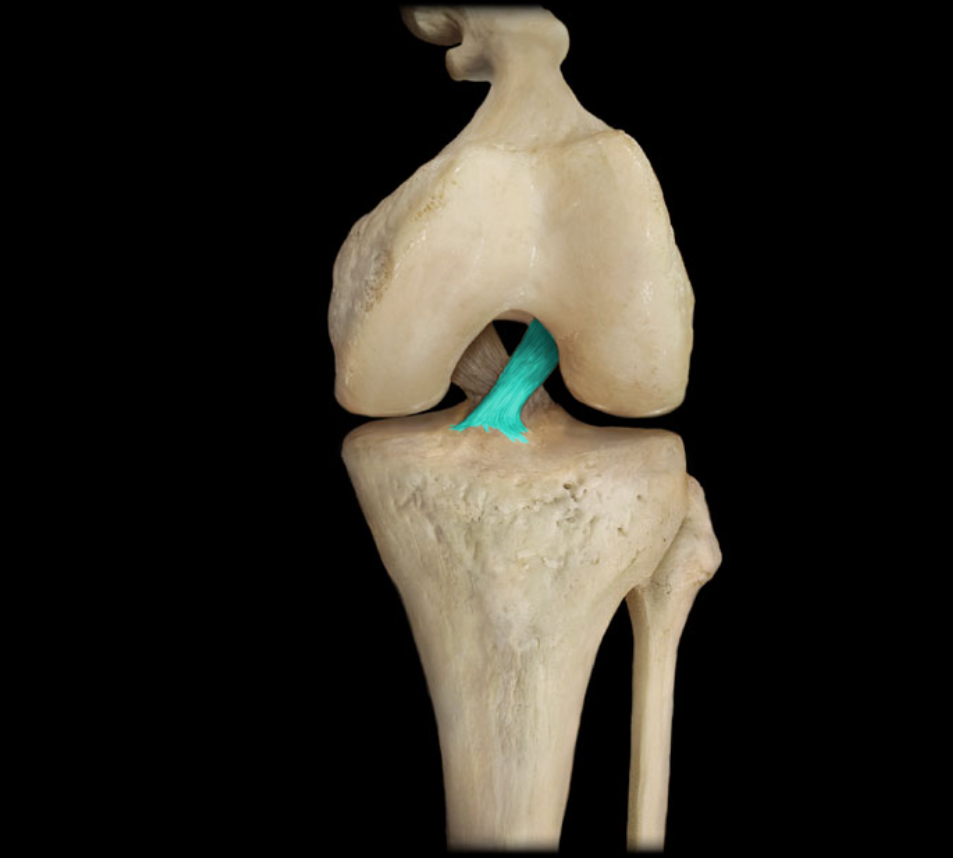

Posterior cruciate ligament

Anterior cruciate ligament